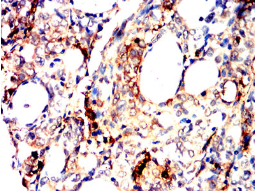

TPSAB1 Mouse Monoclonal antibody[6B611]

Tryptases comprise a family of trypsin-like serine proteases, the peptidase family S1. Tryptases are enzymatically active only as heparin-stabilized tetramers, and they are resistant to all known endogenous proteinase inhibitors. Several tryptase genes are clustered on chromosome 16p13.3. These genes are characterized by several distinct features. They have a highly conserved 3' UTR and contain tandem repeat sequences at the 5' flank and 3' UTR which are thought to play a role in regulation of the mRNA stability. These genes have an intron immediately upstream of the initiator Met codon, which separates the site of transcription initiation from protein coding sequence. This feature is characteristic of tryptases but is unusual in other genes. The alleles of this gene exhibit an unusual amount of sequence variation, such that the alleles were once thought to represent two separate genes, alpha and beta 1. Beta tryptases appear to be the main isoenzymes expressed in mast cells; whereas in basophils, alpha tryptases predominate. Tryptases have been implicated as mediators in the pathogenesis of asthma and other allergic and inflammatory disorders.

Species Reactivity:   Human, Rat

IHC    1/200 - 1/1000